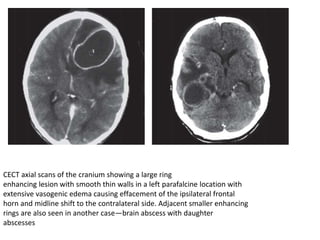

CECT axial scans of the cranium showing a large ring

enhancing lesion with smooth thin walls in a left parafalcine location with

extensive vasogenic edema causing effacement of the ipsilateral frontal

horn and midline shift to the contralateral side. Adjacent smaller enhancing

rings are also seen in another case—brain abscess with daughter

abscesses